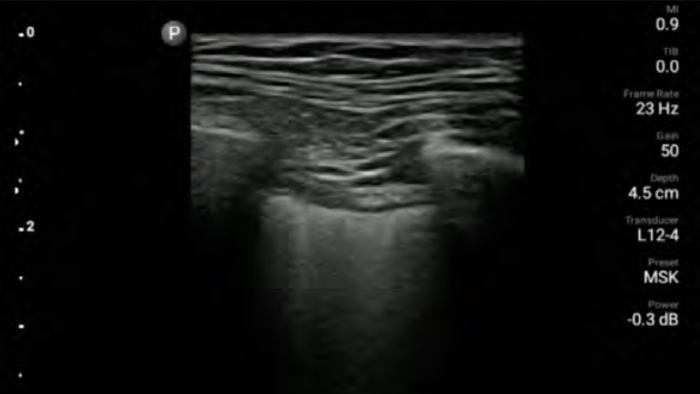

Reduzca las complicaciones en procedimientos guiados por aguja

El ultrasonido portátil Lumify para anestesiología le ayuda a visualizar claramente la definición de los bordes con la colocación de la aguja, los nervios circundantes, los vasos sanguíneos y los planos fasciales.

Transductores Lumify para anestesiología

Transductor de matriz lineal de banda ancha Lumify L12-4